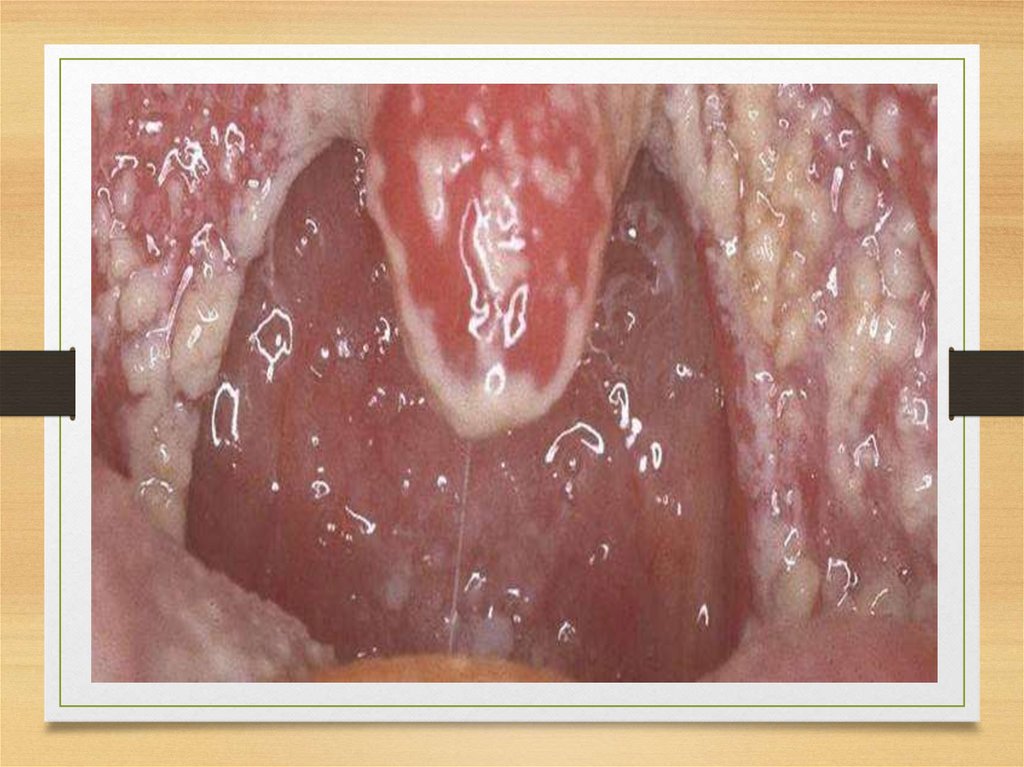

Кандидоз ротової порожнини

Волосиста лейкоплакія язика

Стоматит, хейліт

Кандидоз ротоглотки